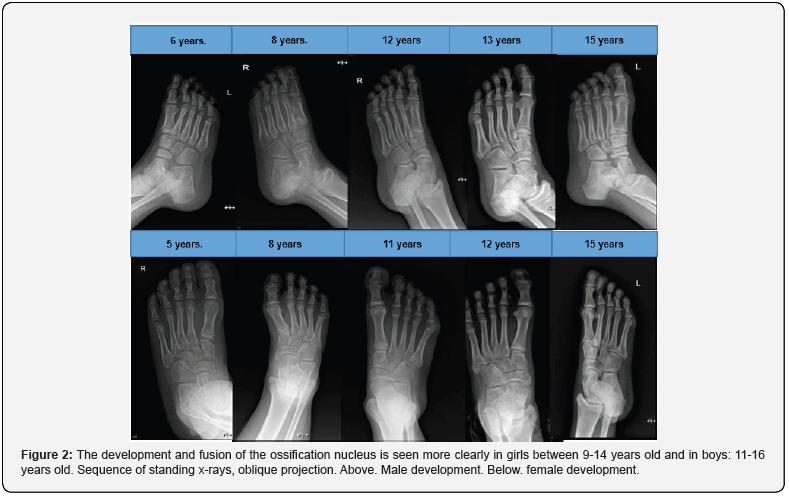

Regarding the anatomy of the fifth metatarsal in the pediatric population, we must remember the appearance of secondary ossification centers that the metatarsals and phalanges have and can be confused with injuries, the rest of the bones are formed from a primary center; The primary one occurs from the eighth month of life and the secondary one is different in each metatarsal (Figure 1) [3]. The importance of the styloid process of the fifth metatarsal in the insertion of the tendon of the peroneus brevis muscle and the lateral cord of the plantar aponeurosis, important in the joint stability of the ankle [4]. The ossification centers begin to appear between 2 months and 2 years and fuse between 13 and 22 years, while the basal styloid process develops between 9 and 11 years in girls and between 11 and 14 years in children, merging two or three years later (Figure 2) [5].